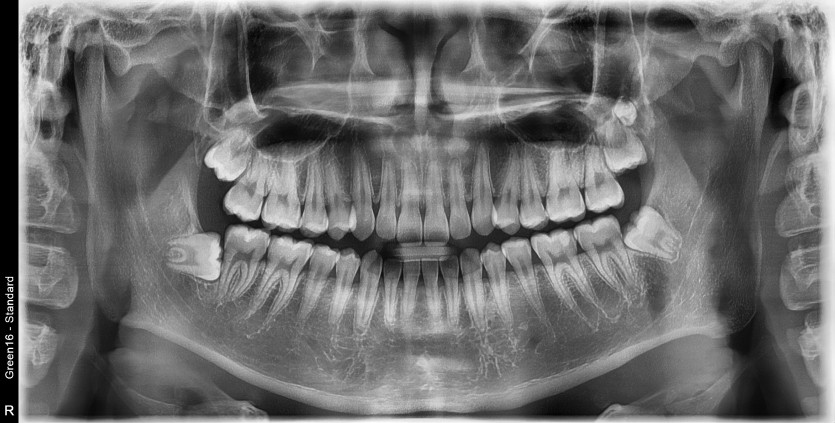

#18,28,38,48 사랑니 발치(#29 과잉치 포함)

구강 외과 전문의가 당일 발치했습니다.